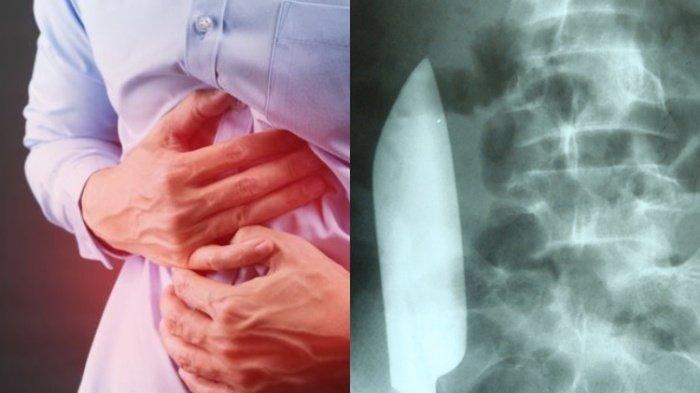

Ilustrasi seorang pria mengeluh sakit perut, syok ternyata ada pisau di dalam perutnya

TRIBUNHEALTH.COM - Fakta ngeri datang dari seorang pria yang mengaku sakit perut, ternyata setelah dilakukan pemeriksaan terdapat sebuah pisau di dalam tubuhnya.

Melansir Surya.co.id, diketahui pisau tersebut memiliki panjang kurang lebih 15 cm.

Keberadaan pisau di dalam perut itu terungkap usai dokter melakukan rontgen.

Setelah dilakukan rontgen, dokter kemudian menemukan ada pisau besar masih ada di dalam dan posisinya melintasi perutnya dari sisi kanan ke kiri.

Tampaknya pisau tersebut tidak melukai organ dalam lainnya, menurut laporan kasus di jurnal Cureus, 2 September 2023.